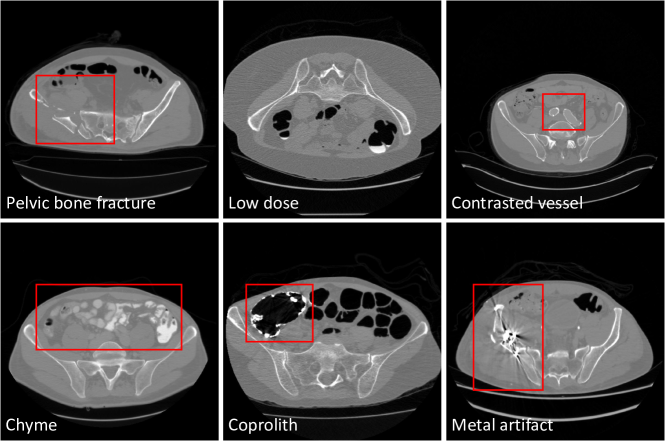

Figure 1: Pelvic CT image examples with various conditions.

To build a comprehensive dataset, we have to deal with diverse image appearance variations due to differences in imaging resolution and field-of-view (FOV), domain shift arising from different sites, the presence of contrasted vessels, coprolith and chyme, bone fractures, low dose, metal artifacts, etc. Fig. 1 gives some examples about these various conditions. Among the above-mentioned appearance variations, the challenge of the metal artifacts is the most difficult to handle. Further, we aim at a multi-class segmentation problem that separates the pelvis into multiple bones, including lumbar spine, sacrum, left hip, and right hip, instead of simply segmenting out the whole pelvis from CT.